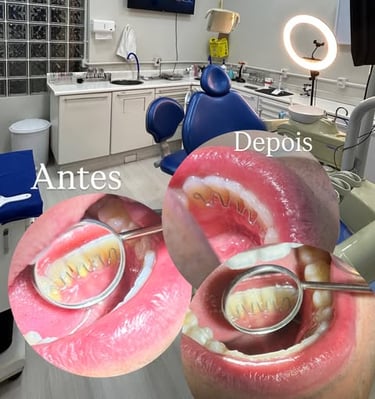

Galeria Sorrisos

Explore os sorrisos transformados com nosso atendimento humanizado e tecnologia.